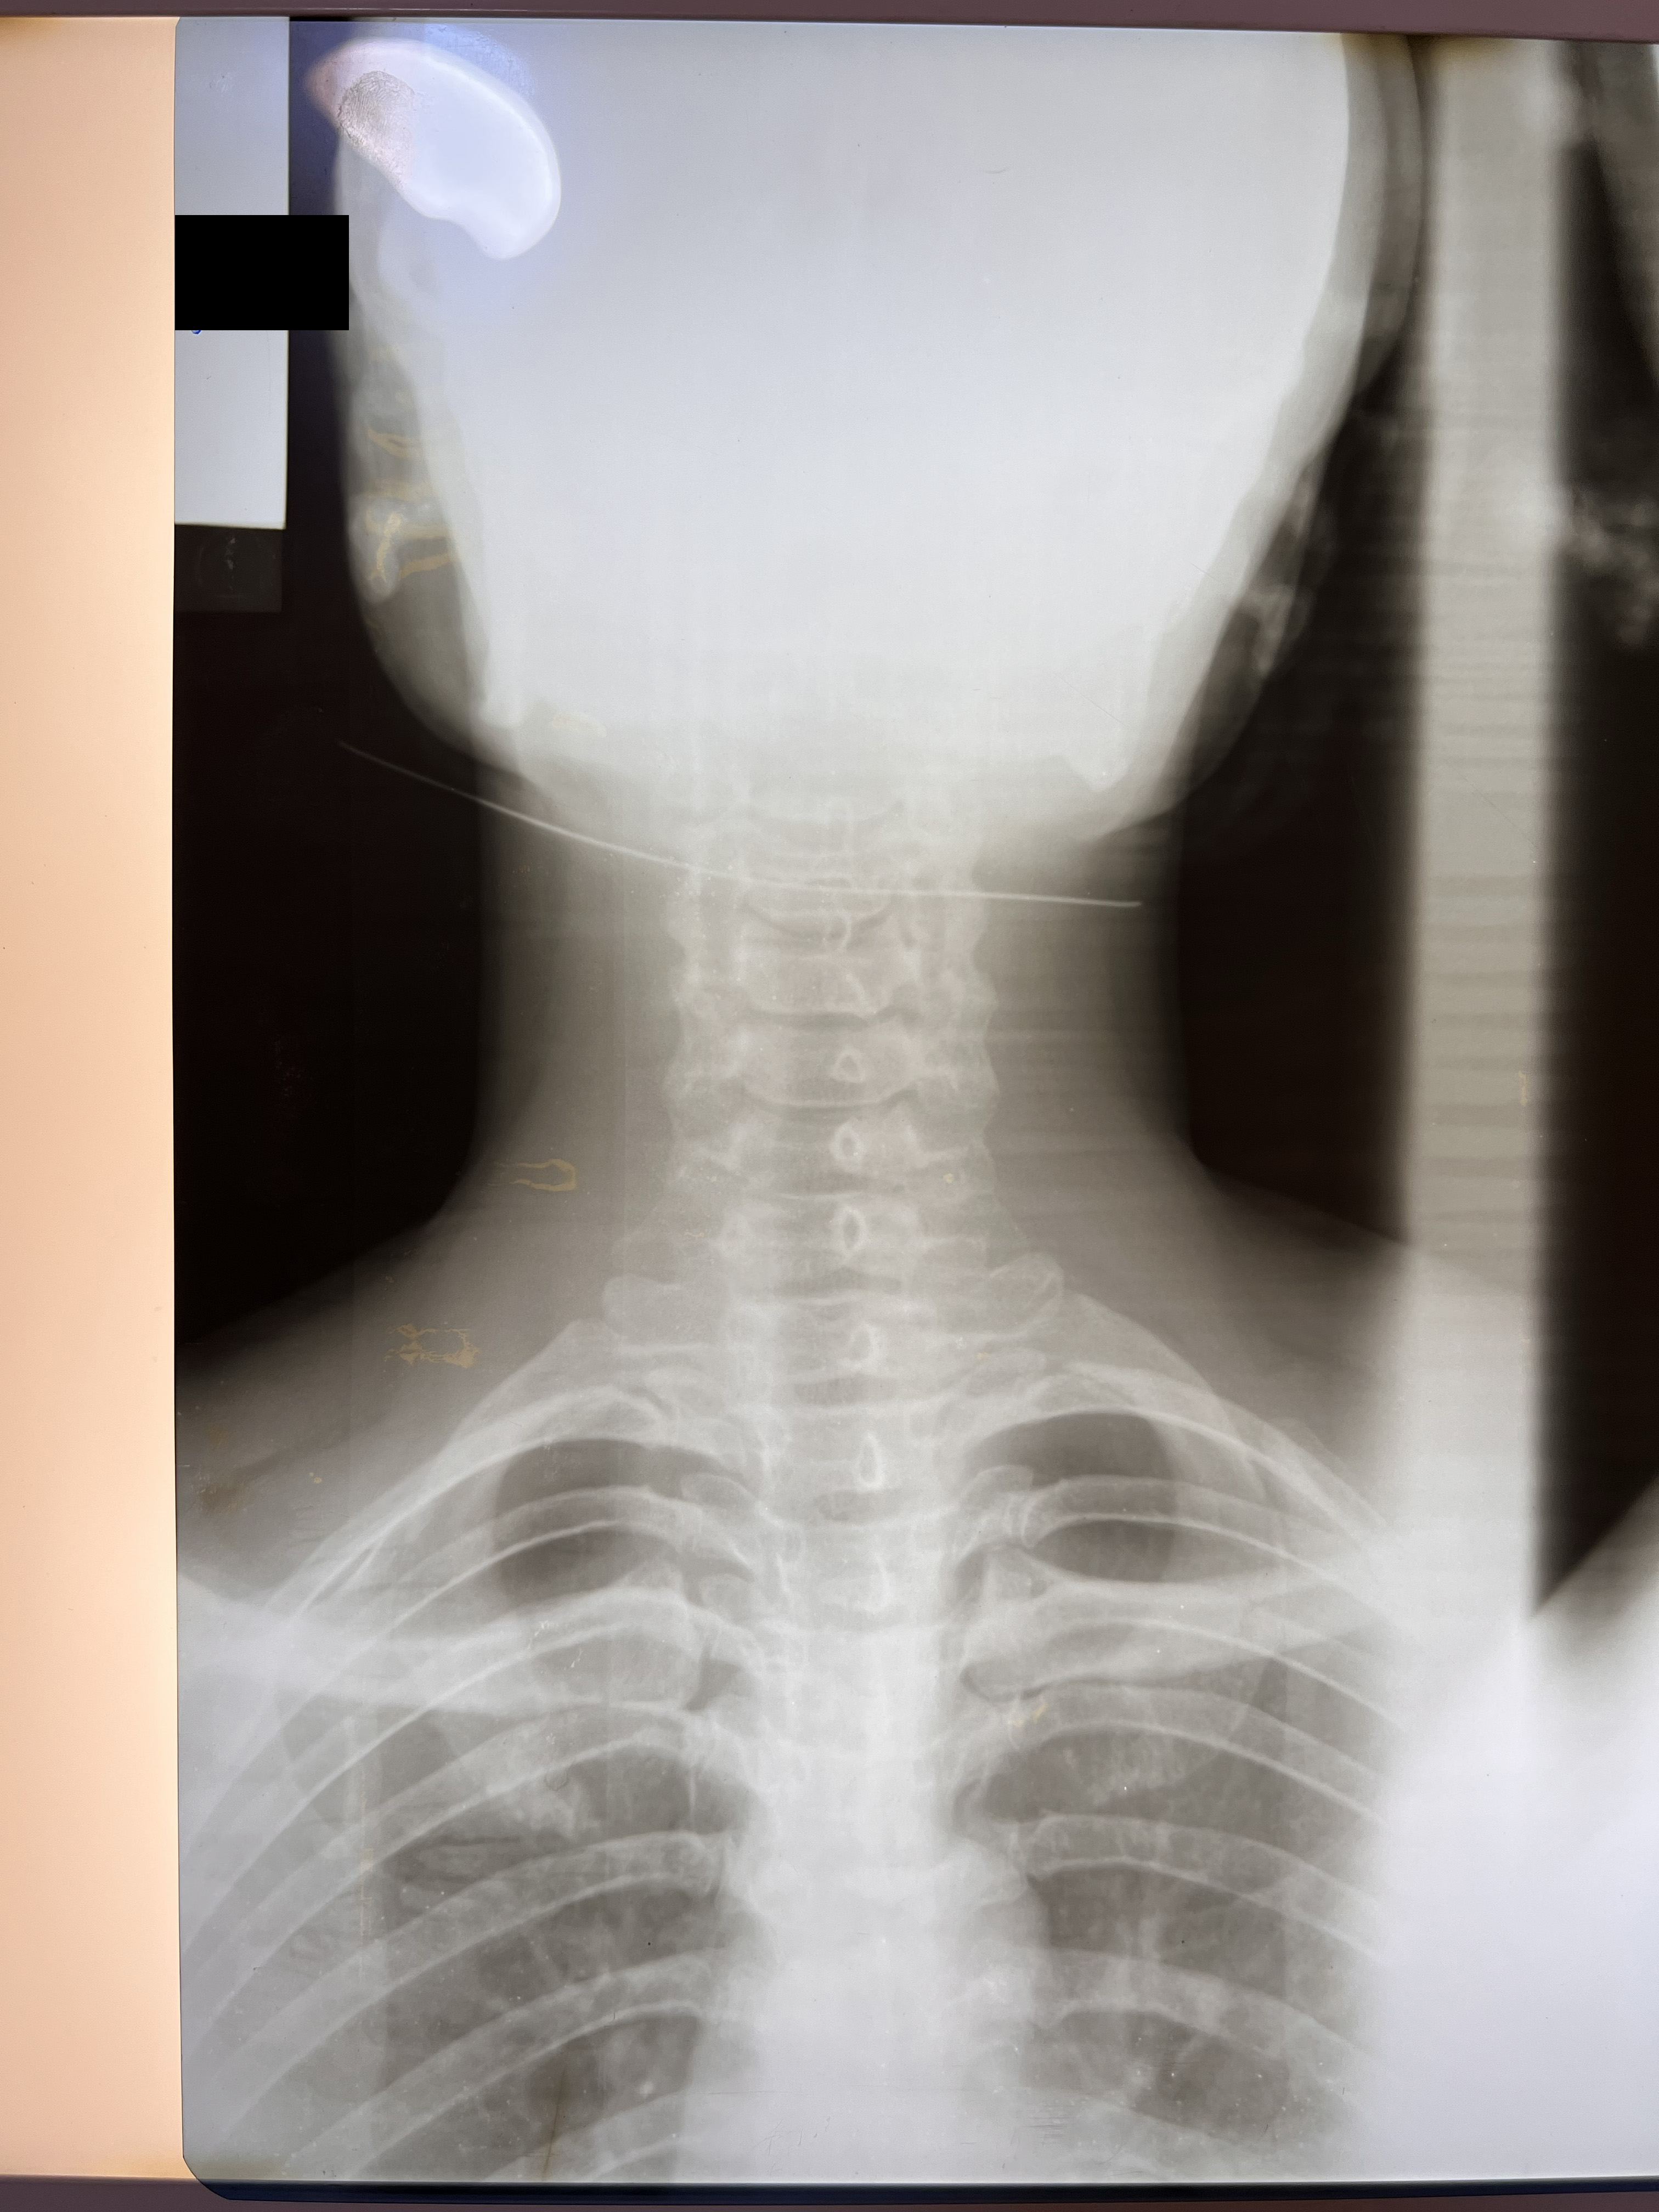

Chiropractic X-Rays

In partnership with Nova Wellness Centre led by Dr Asheley Ashietey in Accra, we conducted chiropractic examinations of 100 women working as kayayei in Kantamanto Market ranging in ages from 15 to 44, with varied experience carrying in the market from those who had been working for a few weeks to some women who had carried bales for 20 years. Nearly every study participant reported significant pain as a result of headcarrying and x-rays indicated spinal deterioration and deformities beginning within months on the job. Such physiological impacts coupled with severely polluted, cramped and violent living conditions set the stage for catastrophic injury.